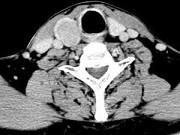

问题 男,43岁,右颈部扪及一包块,CT如图所示,应诊断为()

选项 A.甲状腺腺瘤 B.甲状腺腺癌 C.结节性甲状腺肿 D.甲状腺原发淋巴瘤 E.甲状腺转移瘤

答案 A